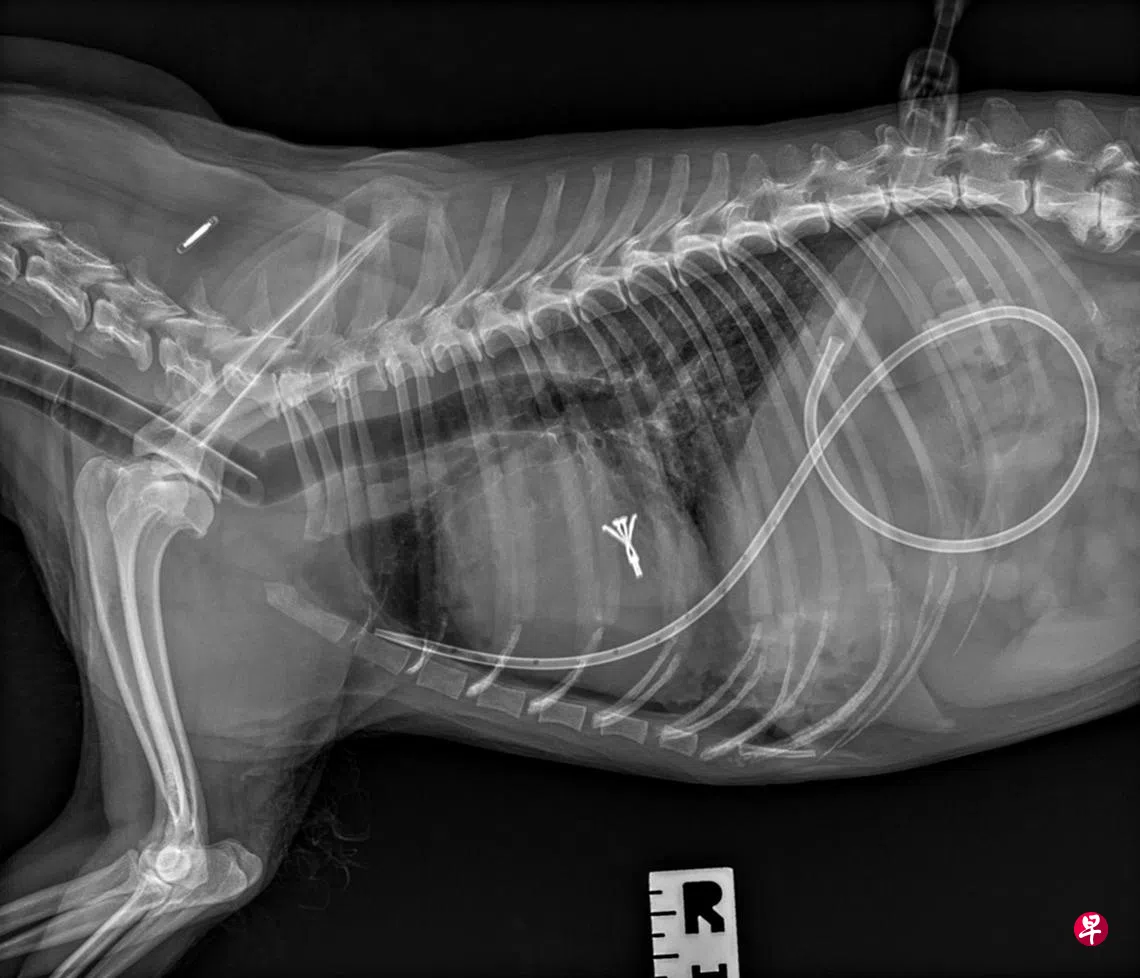

自去年第一起成功病例,他至今已为九只宠物犬成功植入Y型钩子,大大改善心脏瓣膜的功能。手术属微创手术,与传统的开胸手术不同,仅需在心脏下方开个小孔导入钩子,无需让心脏停止跳动,降低手术风险。手术后的复元期也相对较短,一般两天后宠物犬就可出院。

这项技术源于美国在人体医学中的应用,中国公司把钩子进行小型化改造,以适应宠物市场的需求。动手术过程中,除了要确保钩子准确地拴夹,避免脱落对心脏瓣膜造成二次伤害,还必须严控麻醉药剂,因为这些宠物犬的心脏本来就很弱,很可能无法熬过麻醉用药。

人类也面对心脏瓣膜功能疾病,多年来的治疗方法是植入Y型钩子,拴夹起松弛的心脏二尖瓣膜。这项技术后来转移到宠物犬的身上,但只在美国、日本、韩国和中国进行。本地宠物犬如果患上同样疾病,只能到海外就医,但往往因狗龄大或健康状况不理想而作罢。